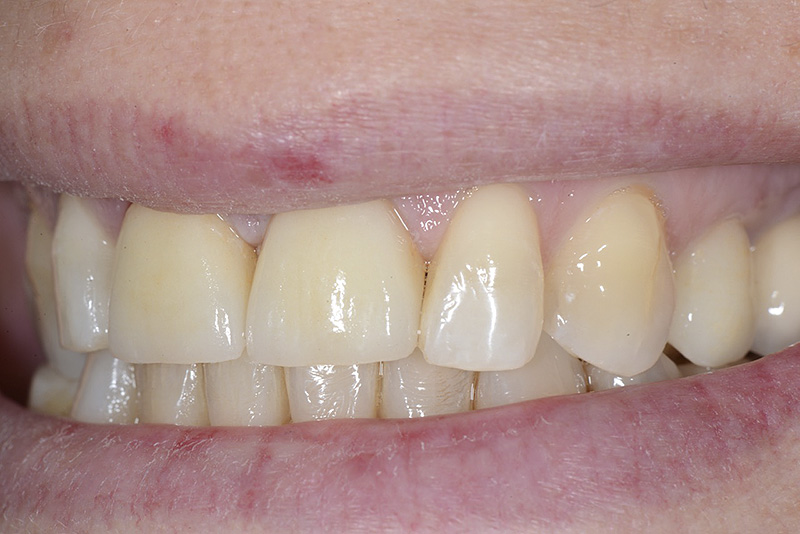

Vengono utilizzati 2 tipi di provvisori: il primo, cementato ai denti vicini, viene utilizzato dal momento dell’estrazione del dente fino ad impianto osteointegrato (circa 6 mesi); il secondo, avvitato direttamente all’impianto, ha una funzione di prova estetica ma soprattutto di guida per la maturazione dei tessuti gengivali peri-implantari portandoli verso la maturazione completa prima di posizionare la corona finale in disilicato di litio.